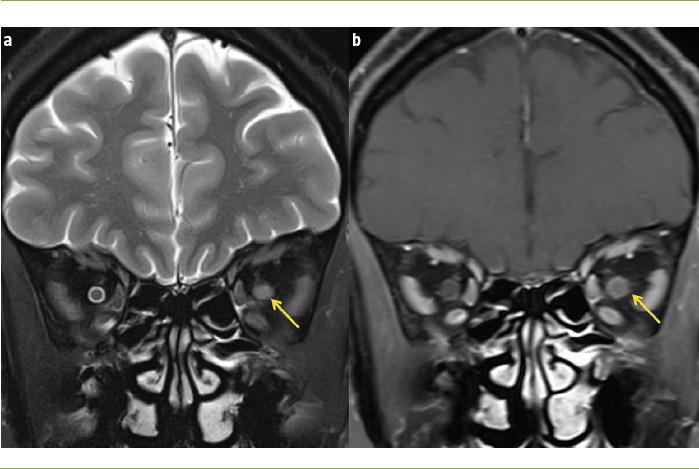

The main causes of optic neuritis (ON) are multiple sclerosis (MS), neuromyelitis optica spectrum disorder (NMOSD) and myelin oligodendrocyte glycoprotein antibody disease, also known as MOGAD. When all screening is negative, we can speak of idiopathic ON, although this diagnosis should be provisional. ON can be diagnosed clinically and paraclinical tests are not routinely required to confirm it. However, tests such as magnetic resonance imaging (MRI), visual evoked potentials (VEP) and optical coherence tomography (OCT) can lend support to the diagnosis if the clinical presentation is atypical. The use of new MRI sequences, OCT, multifocal VEPs and the determination of neurofilaments has allowed ON to be used as a model for remyelination and neuroprotection, leading to phase II clinical trials. Some of these drugs, such as opicinumab, clemastine, phenytoin or simvastatin, have shown positive results; however, their clinical effect remains to be defined. It is accepted that corticosteroids do not improve the long-term prognosis of ON, although some retrospective studies suggest that there is a therapeutic window from the onset of symptoms. Plasmapheresis has also been shown to be effective in patients with ON. In this review we will address basic aspects of the management of ON, in the fundamental context of MS, NMOSD and MOGAD, with emphasis on etiopathogenic, diagnostic, prognostic and therapeutic developments.

视神经炎(ON)的主要病因包括多发性硬化症(MS)、视神经脊髓炎谱系障碍(NMOSD)以及髓鞘少突胶质细胞糖蛋白抗体病,也称为MOGAD。当所有筛查均为阴性时,我们可以称之为特发性ON,不过这一诊断应为临时性的。ON可通过临床诊断,通常无需辅助检查来确诊。然而,如果临床表现不典型,诸如磁共振成像(MRI)、视觉诱发电位(VEP)和光学相干断层扫描(OCT)等检查可为诊断提供支持。新型MRI序列、OCT、多焦VEP的应用以及神经丝的测定已使ON能够作为再髓鞘化和神经保护的模型,从而开展II期临床试验。其中一些药物,如opicinumab、氯马斯汀、苯妥英或辛伐他汀,已显示出阳性结果;然而,它们的临床效果仍有待确定。尽管一些回顾性研究表明从症状出现开始存在一个治疗窗口期,但普遍认为皮质类固醇并不能改善ON的长期预后。血浆置换在ON患者中也已显示出有效性。在本综述中,我们将探讨在MS、NMOSD和MOGAD的基本背景下ON管理的基本方面,重点关注病因、诊断、预后和治疗进展。